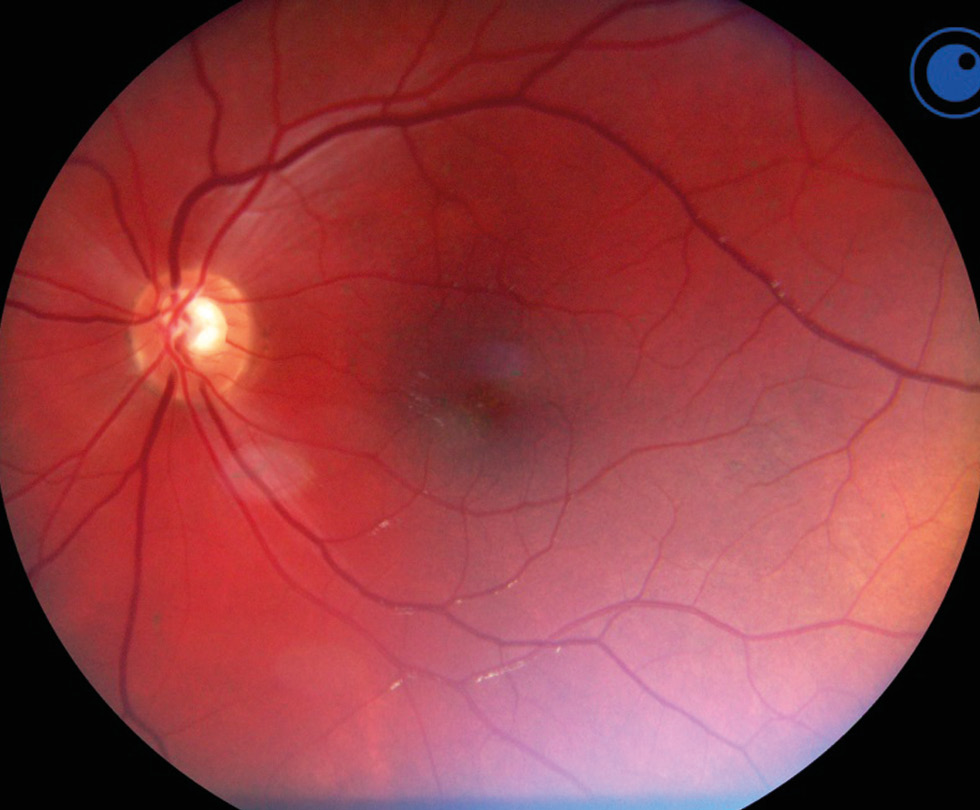

RESULTS: This article presents the clinical case of postoperative choroidal detachment in a child with Sturge–Weber–Crabbe syndrome after microinvasive non-penetrating glaucoma surgery. Against the background of the existing anomalies in the development of an optic disc after antiglaucomatous intervention for decompensated glaucoma, after the normalization of IOP, the patient developed choroid detachment with exudative retinal detachment the next day of operation. After conservative therapy involving bed rest and double instillation of mydriatics for 1 month, the situation was completely resolved and his vision was restored to 1.0.

DISCUSSION: The atypicality of our clinical case of CD lies in the overly pronounced exudative component. In addition to the classic CD vesicles, we observed high exudative retinal detachment as well as high retinoschisis, which is extremely atypical for classical CD. Considering the characteristics of congenital syndrome, it is necessary to accurately differentiate atypical CCA from the rare choroidal effusion syndrome, which also includes CCA with retinal detachment, but does not present with retinoschisis. Against the background of conservative therapy with bed rest and two instillations of mydriatics for 1 month, the situation was completely resolved, and the patient’s vision was restored to 1.0. In the treatment of such patients, it is always necessary to consider their individual anatomical features as well as to understand the detailed pathogenesis of the complications that arise before rushing to repeat surgery.